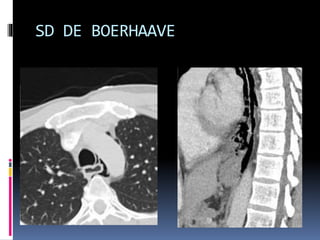

RUPTURA DO ESÔFAGO

 SD DE BOERHAAVE - perfuração espontânea do esôfago.

 Causa rara, mas potencialmente fatal

 Diagnóstico diferencial: SCA

 Q.C. clássico (mas nem sempre presente): vômitos

seguidos de dor torácica de forte intensidade, dispnéia,

enfisema subcutâneo e rápido colapso circulatório. Dor no

ombro e/ou epigástrica podem estar presentes.

 Após 12h do início do quadro, é comum achado de febre e

sinais de sepse (mediastinite).

 EX físico: ↓sons pulmonares, enfisema subcutâneo tórax e

pescoço.

 Alt. Radiológicas: pneumomediastino, hidropneumotórax,

derrame pleural e alargamento do mediastino

SD DE BOERHAAVE